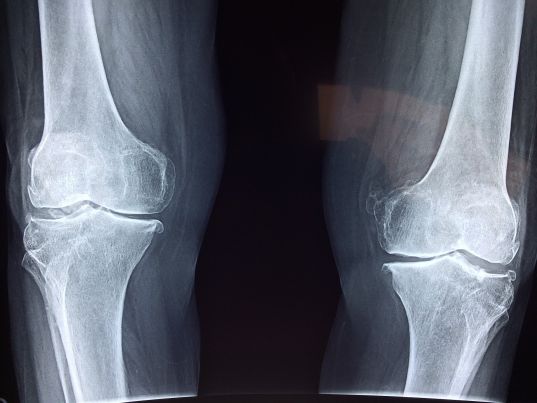

图片来自CC0 Public Domain。